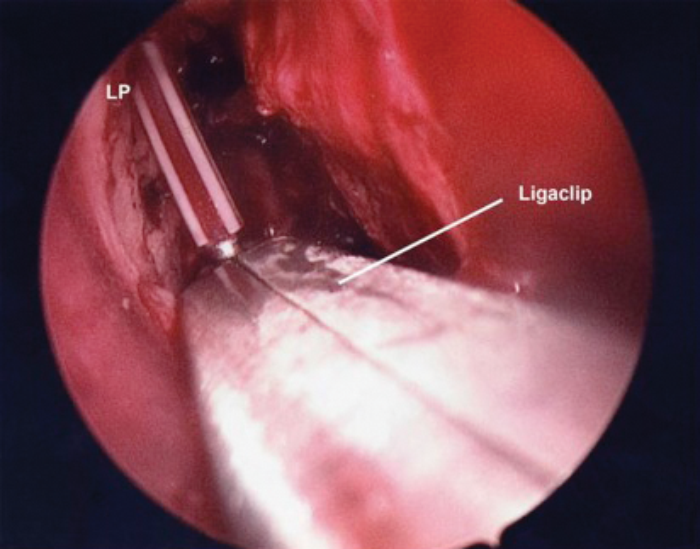

A wide nasolacrimal window is created. Silastic lacrimal stents are then placed via both upper and lower canaliculi, retrieved endonasally (Figures 7a & b) and tightened over a 18 gauge venflon sheath / silastic tubing (Figure 8) to prevent upward migration of the stent knot. The stent loop is ensured not to be too tight as it may cheese wire through the puncta. We prefer using ligaclips to stabilise the stents (Figures 9a & b) in place of knots to avoid any risk of slippage of the knot leading to stent laxity. The nasal mucosa is trimmed and folded back to cover the exposed bone and haemostasis achieved with suction diathermy.

MT - Middle Turbinate S - Stents

Figure 9a (top) & 9b (above). Stent stabilisation with Ligaclips.